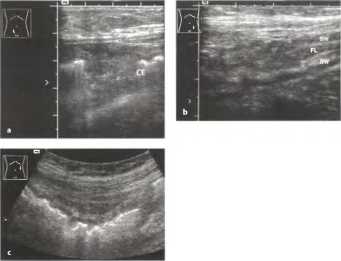

Сонографическая картина хронического тяжелого Helicobacter pylori-положительного гастрита типа В представлена на рис. 13: Легкое или умеренное утолщение или гиперплазия складок. Толщина складки часто достигает 20 мм, с четкой дифференцировкой гребней и впадин

Рис. 13. Тяжелый гастрит типа В: заметно утолщенная стенка желудка с четкой слоистой структурой (гипоэхогенный слой - эхогенный - гипоэхогенный, курсоры). Просвет почти облитерирован, определяется лишь маленький высокоамплитудный воздушный эхо-сигнал и небольшое количество жидкости (FL).

Заполнение тела желудка жидкостью значительно улучшает визуализацию.